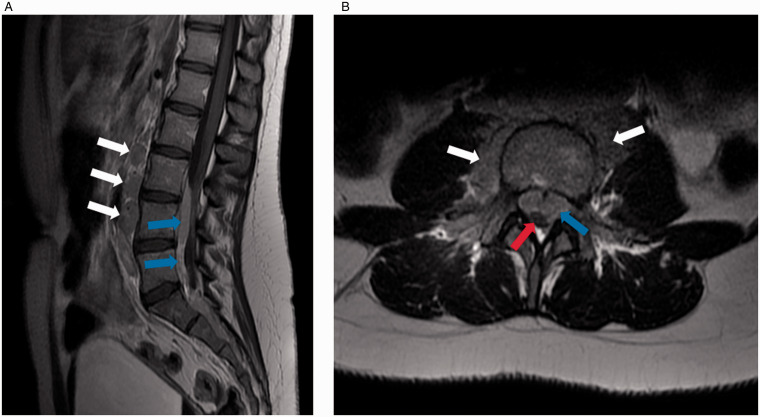

Hodgkin lymphoma (HL) can present with extra-nodal disease, but spinal cord compression is exceptionally rare. We describe a 15-year-old presenting with hip/back pain with normal initial examination. Persistent pain and raised inflammatory markers prompted further investigation with MRI, which revealed an epidural mass causing spinal cord compression. On examination, there was no palpable lymphadenopathy or cauda equina syndrome, but absent lower limb reflexes were noted. Following multidisciplinary discussion, it was determined that cauda equina syndrome was imminent and therefore surgical debulking was undertaken, both to prevent this complication and establish a diagnosis. At surgery, the tumor was highly vascular. Frozen section confirmed lesional material. Following surgery, and given the frozen section findings, a short course of steroids was commenced to reduce any peri-surgical edema. Unfortunately, histopathology was ultimately non-diagnostic, due to failure of immunohistochemistry on technically challenging material. Consequently, ultrasound-guided excision biopsy of a (non-palpable) cervical lymph node was performed five days later; histopathology showed typical effacement of the normal architecture and a conspicuous population of CD15/CD30-positive larger pale cells present, confirming nodular sclerosis classic HL, despite recent steroids. We review the available literature for HL presenting with spinal cord compression and describe the challenges for diagnosis and initial management in such cases.